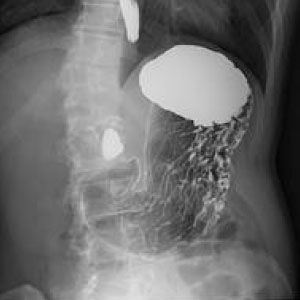

エックス線を利用して体内をリアルタイムに見ながら検査を行います。胃のバリウム検査や腸のバリウム検査、骨折、脱臼の整復術や神経根、脊髄腔造影、嚥下造影(VF)など多岐にわたり検査を行っております。